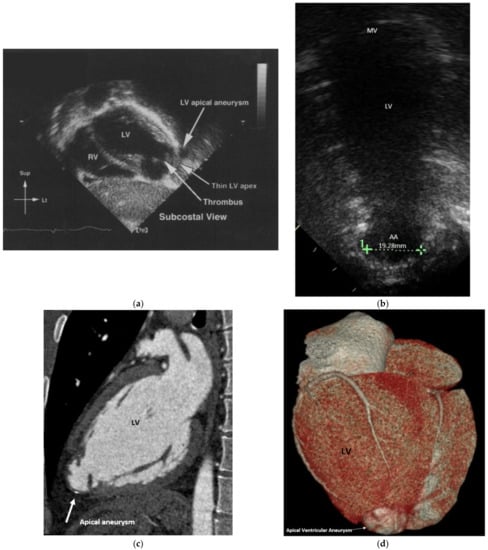

2. Case Report